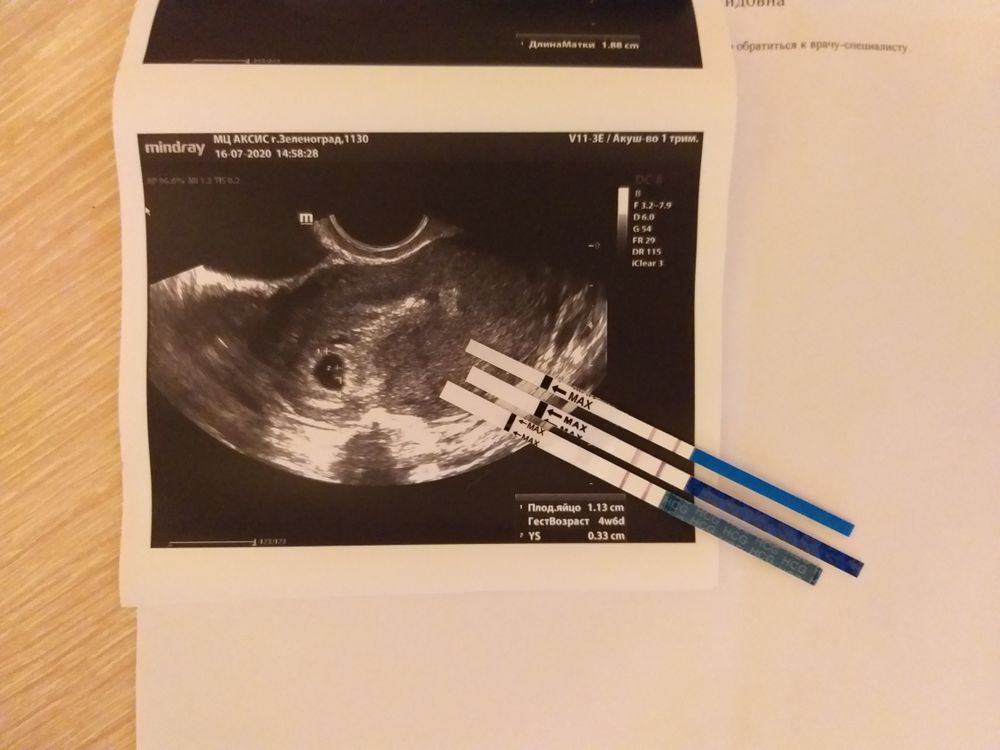

Последняя запись моя была о сбоях в цикле после ЭКО и я до последнего так и думала, что всё таки это гормональный сбой. Но перед приемом к гинекологу я решила, что надо сделать тест на всякий случай, чтоб было что отвечать врачу, когда она спросит 🤷♀️ Утром 16 июля я без каких-либо мыслей о двух полосках, сделала тест и отвернулась от него почистить зубы. Повернувшись пару минут спустя, я увидела тест с яркими двумя полосками. Я не поверила своим глазам! "Нет, это ошибка какая-то" - крутилось в моей голове. Ничего не сказав мужу, я побежала перед работой в аптеку и купила ещё 2 теста разных фирм. И сделала их на работе в обед. Полоски проявились сразу же вместе. Сомнений не было. Я беременна!!! 🙈❤ не дожидаясь приема гинеколога, я побежала делать платно УЗИ. И оказалось, что правда, уже в матке было плодное яйцо, желточный мешочек. По рекомендации врача я сразу вернула прием дюфастона, плюс витамины. В тот же вечер я рассказала мужу. Сказать что он был в радостном шоке, это ничего не сказать 😂 мы оба были ошеломлены и счастливы одновременно.